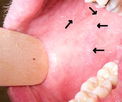

Oral Health Illustrative image of the article Bitter Taste in Mouth: 19 Causes & How to Treat Bitter Taste in Mouth: 19 Causes & How to Treat Illustrative image of the article Numb Lips, Mouth or Tongue: 12 Causes & What to Do Numb Lips, Mouth or Tongue: 12 Causes & What to Do Illustrative image of the article White Tongue: 6 Causes & How to Get Rid of It White Tongue: 6 Causes & How to Get Rid of It Illustrative image of the article Bump on the Roof of the Mouth: 9 Causes (& What to Do) Bump on the Roof of the Mouth: 9 Causes (& What to Do)